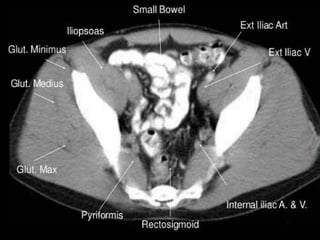

CT cross sectional anatomy.